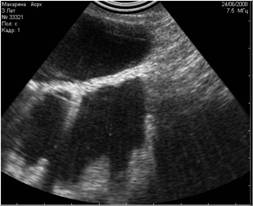

![]() |

Рис. 9. Истинные эхоакустические тени, возникающие позади конкрементов в мочевом пузыре. |

Рис. 10. А вот и сами камни. |